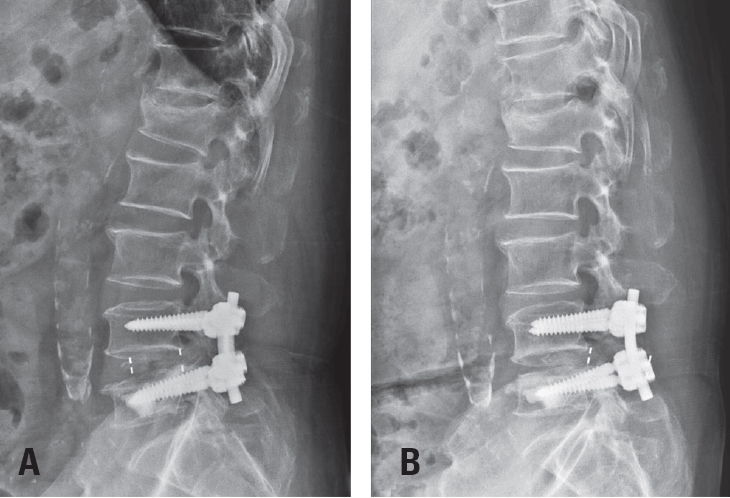

Postoperative imaging was essential for evaluating surgical outcomes. Standard radiographs and computed tomography (CT) scans were used to assess screw position and integrity. Mechanical failures—including pull-out and screw loosening—were identified by the appearance of a halo around the screw, indicating loss of fixation.10) Fig. 1 shows a typical pull-out, where the screw disengages from the vertebral body, whereas Fig. 2 demonstrates screw loosening, identified by the halo sign on CT imaging.

The incidence of mechanical failures was systematically recorded, comparing patients with cement-augmented pedicle screws to those without. Failures were classified into three categories: pull-out, screw loosening, and cage protrusion— the latter defined as displacement of the implanted cage beyond the vertebral body margins (Fig. 3). Fusion status was also evaluated using follow-up radiographs and CT scans. Successful fusion was defined as continuous bone bridging across the intervertebral space without radiolucent lines surrounding the implant. Representative CT images of successful fusion are shown in Fig. 4.

Fig. 3.

(A) Immediate postoperative radiograph showing pedicle screw and cage placement. (B) Follow-up radiograph at two months demonstrating cage protrusion, with the cage extending beyond the vertebral body margins.

Fig. 3. (A) Immediate postoperative radiograph showing pedicle screw and cage placement. (B) Follow-up radiograph at two months demonstrating cage protrusion, with the cage extending beyond the vertebral body margins.